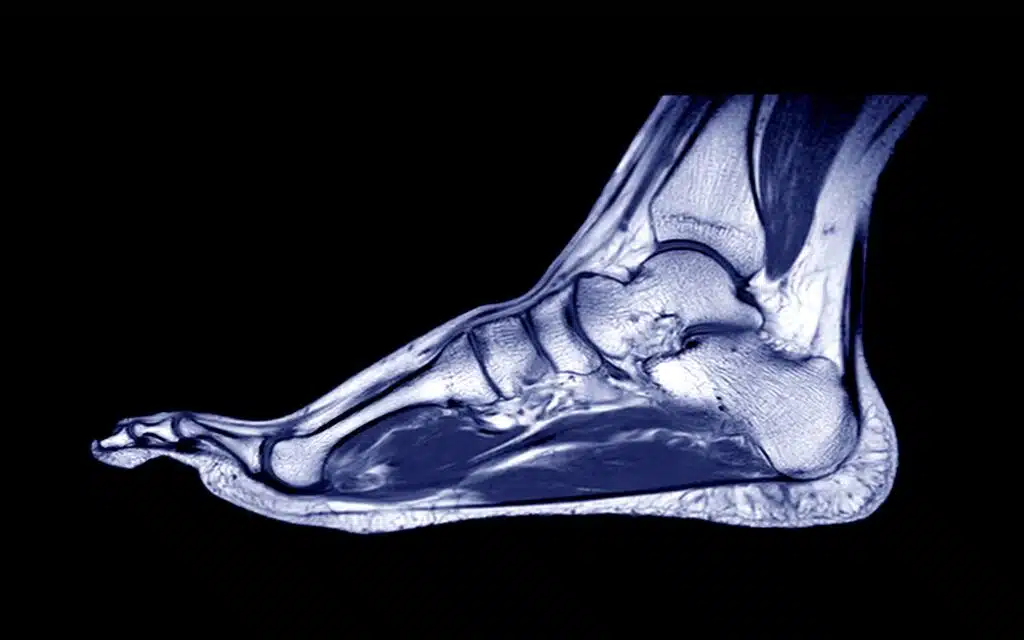

Ankle & Foot MRI